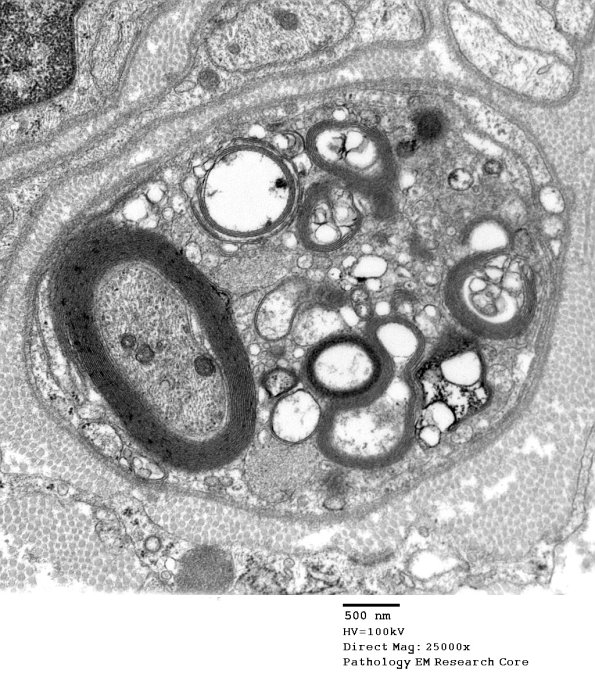

5B1,2 In this case there is demyelination of otherwise normal appearing myelin with axonal preservation. (electron micrograph)